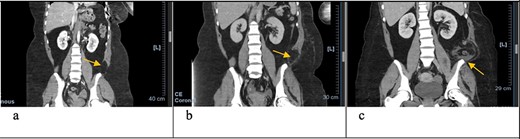

Coronal CT scan with arrows pointing to internal and external oblique defects in June (a), August (b) and September (c); panel (a) shows rupture between internal and external oblique muscles at the attachment point of the quadratus lumborum; panel (b) shows fat stranding, suggesting inflammation of the epiploic appendage, and may be an early sign of delayed traumatic wall hernia; panel (c) shows herniation through the muscular defect, with the descending colon without obstruction.

In June, the patient’s CT imaging demonstrated a left posterolateral muscular defect of the fascia and external and internal obliques (Figs 1a and2a). Follow-up CT in August showed an increase in size with noticeable atrophy of the muscles with fat stranding (Figs 1b and2b). The atrophy may be due to the month-long period where she was immobile in the SICU. Muscle atrophy combined with the inciting event could be indicators for delayed TAWH, especially for those with prolonged hospital stays [3, 10]. When the hernia presented, CT imaging showed the appearance of fat and descending bowel (Figs 1c and 2c). We theorize that our patient’s MVC resulted in an initial defect or tear in the fascia, internal and external obliques. Her prolonged stay compounded the problem through muscle atrophy and peritoneal stretching. These factors, coupled with the activities of daily life, lead to the delayed presentation of traumatic lumbar hernia. Although lumbar hernias may rarely cause SBO, they may be indirectly linked.